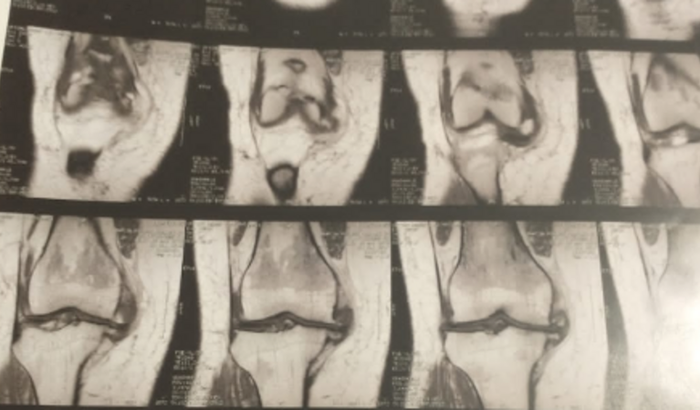

Amigos, por favor, preciso muito pedir a ajuda de todos vocês! Sei que todos nós achamos que temos problemas, mas se você tem saúde, acredite, você tem apenas dias difíceis! Ela precisa fazer um exame importantíssimo, ressonância magnética , esse exame vai diagnosticar a causa dela não poder caminhar com facilidade .... impossibilitando-a de andar sem companhia, pois ela pode cair e se machuca ,ela também sentir muitas dores principalmente quando o joelho sai do lugar e ao caminhar Segundo pesquisas iniciais, acreditamos que custará em torno de R$700, Sei que ninguém dispõe desse valor para "ajudar ninguém", mas sei também que se todo mundo ajudar um pouquinho, contribuindo ou compartilhando, não é nada impossível. Por favor, ajudem!!! Agradeço a todos leram essa mensagem com atenção e carinho.